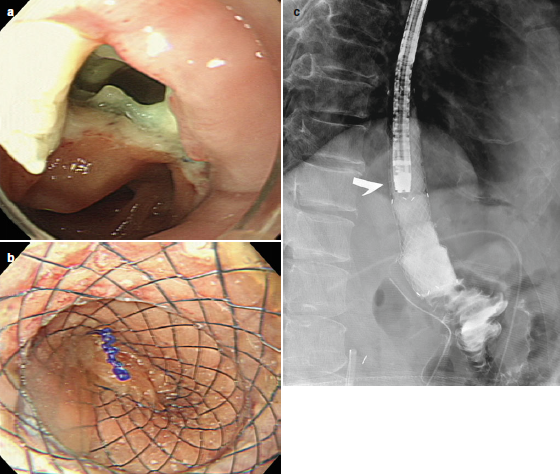

Prótesis:

- Existen prótesis metálicas autoexpandibles totalmente cubiertas, prótesis metálicas autoexpandibles parcialmente cubiertas y prótesis plásticas.

- Vienen de diferentes tamaños y diámetros y deben ser lo suficientemente largas para cubrir 3-5 centímetros proximal y distal al defecto.

- El procedimiento se realiza bajo fluoroscopia y visualización endoscópica. En 48-72 horas se coloca contraste para verificar que no existan fugas y comenzar la dieta oral.

- La complicación más frecuente es la migración de la prótesis.